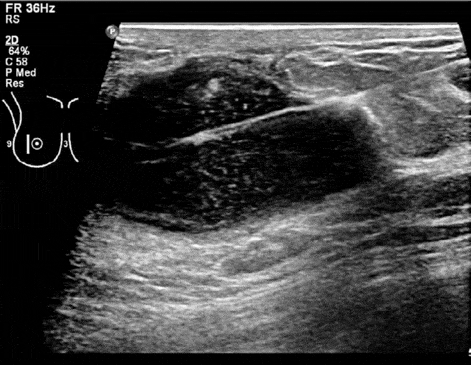

Ancak bu abselere ultrason ya da tomografi eşliğinde önce bir iğne ile girilerek sonra da drenaj katateri yerleştirilerek tedavi edilebilirler. Genel anestezi gererkmeden sadece lokal anestezi ile bu işlem yapılabilir. Takılan kateter aracılığı ile abse boşaltılır. Katater abse sıvısı belli bir miktarın altına inene kadar çıkarılmaz.